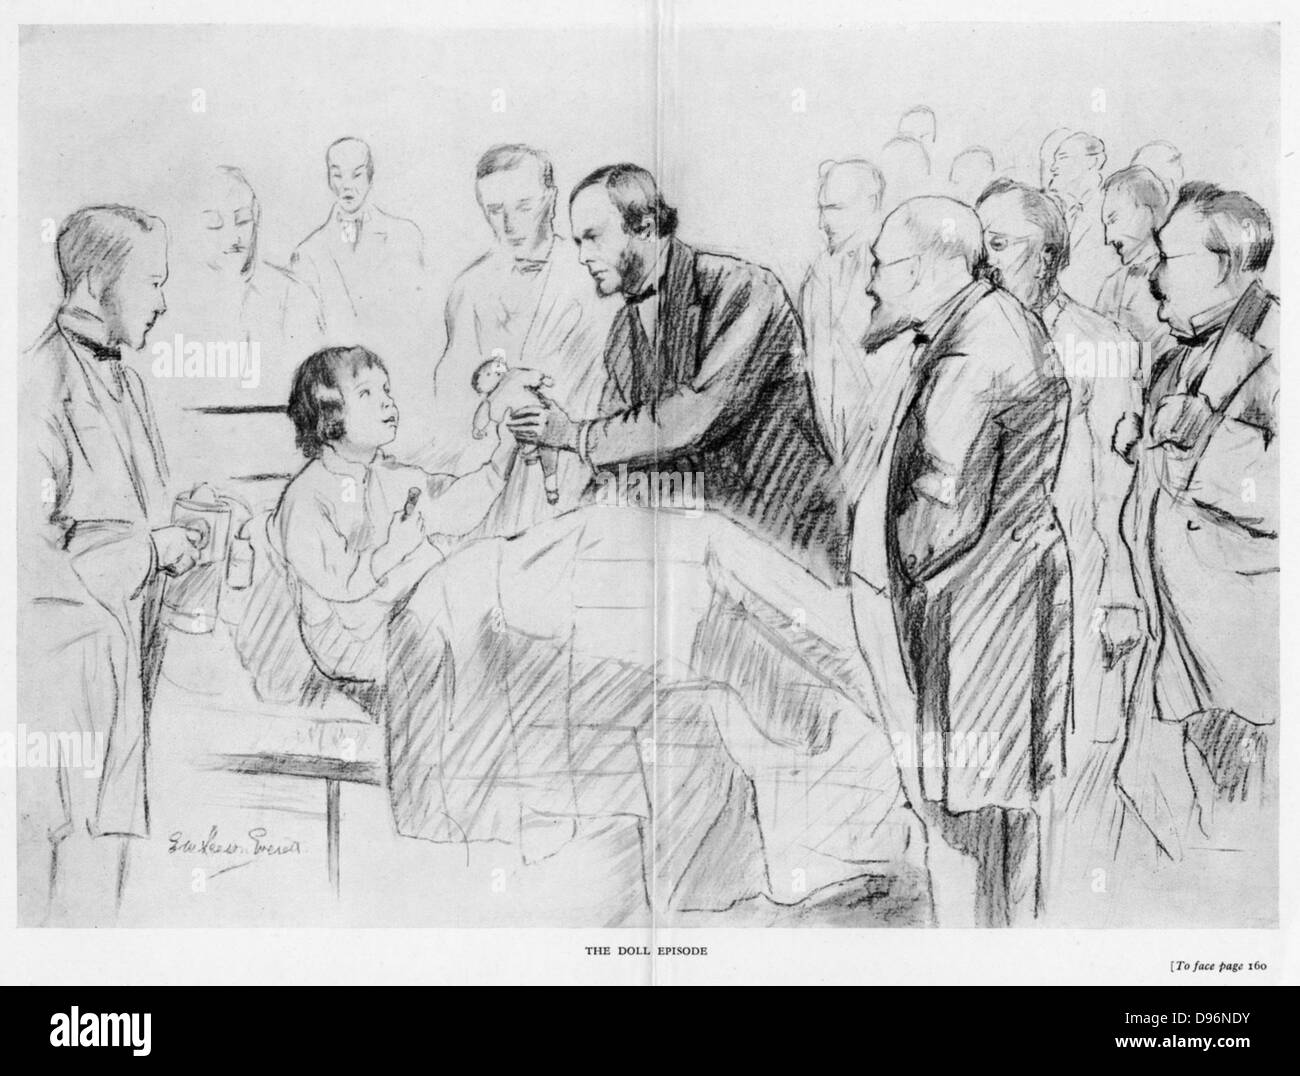

RMD96NDY–Joseph Lister (1827-1912), chirurgo inglese, sul suo ward round in Glasgow Royal Infirmary c1867. Un pioniere della chirurgia antisettica, egli fu in grado di annunciare in 1867 che i suoi pupilli fosse stata chiara della sepsi per 9 mesi.sulla sinistra un assistente che tiene il Lister di spruzzo di vapore che produce uno spruzzo di acido carbolico (fenolo) laden vapore. Il paziente è di consegnare il Lister ha il suo Broken Doll e ha seminato la sua gamba posteriore su di lei. Dopo schizzo a matita.